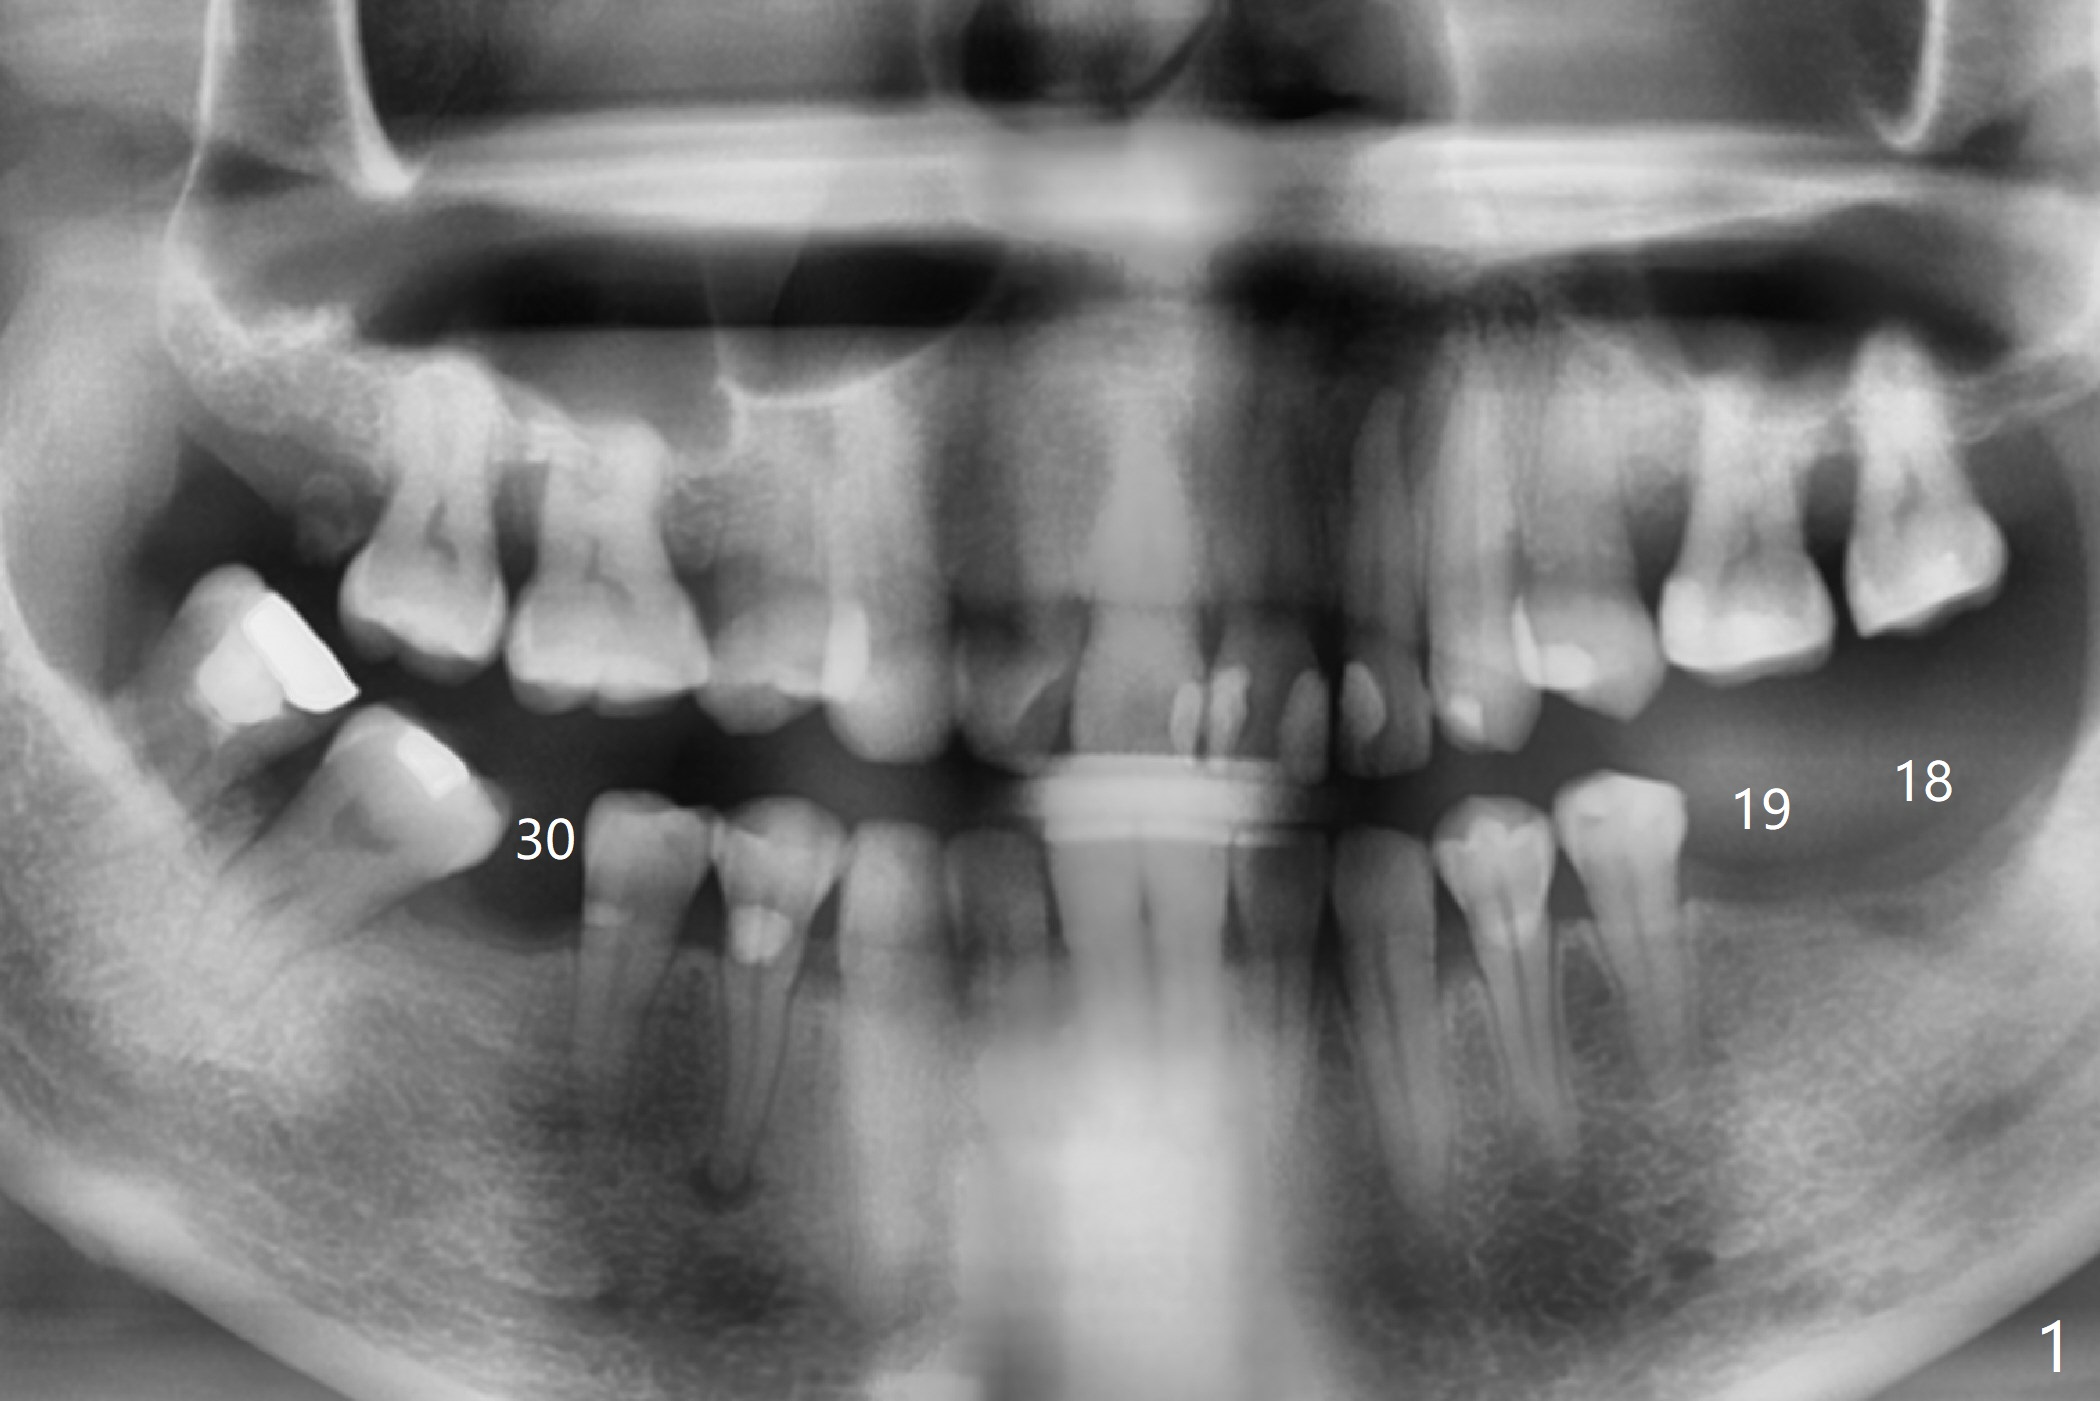

A 48-year-old woman, dentophobic, presents to clinic with request of redo #8,9 composite, which have dislodged twice in the last 6 months. Restoration failure is at least in part due to partial edentulism (#18,19,30, Fig.1). After discussion, she agrees to have implants at #18 and 19 first with guide (Fig.2,3). An ideal treatment plan for #30 (narrow mesiodistal space) would be extraction of #32 (ML fracture), uprighting of #30 and placement of a normal diameter implant. Considering dentophobia and living far from the office, a practical option will be a 3x12 mm 1-piece implant (Fig.4).